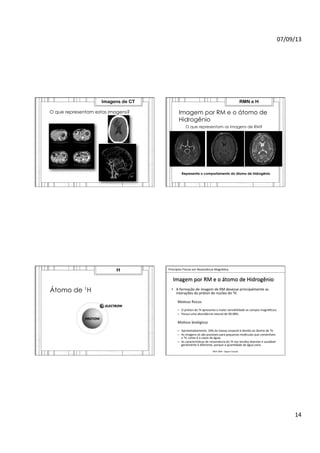

O que representam estas imagens?

Imagens de CT

Imagem por RM e o átomo de

Hidrogênio

O que representam as imagens de RM?

Representa o comportamento do átomo de hidrogênio

RMN e H

Átomo de 1H

Imagem

por

RM

e

o

átomo

de

•  A

formação

devesse

principalmente

as

interações

do

próton

núcleo

¹H.

Mo>vos

Jsicos

–  O

¹H

apresenta

maior

sensibilidade

campos

magné>cos;

–  Possui

uma

abundância

natural

99,98%.

biológicos

–  Aproximadamente,

10%

da

massa

corporal

é

devido

ao

¹H;

–  As

imagens

só

são

possíveis

para

pequenas

moléculas

que

contenham

¹H,

como

casos

água;

caracterís>cas

ressonância

nos

tecidos

doentes

saudável

geralmente

diferente,

porque

a

quan>dade

água

varia